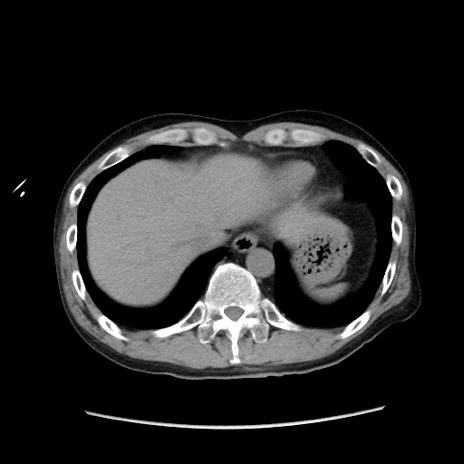

症例37(横断像)

【症例】40歳代 男性

【主訴】腹痛

【現病歴】4時間ほど前に電車に乗車中に臍部上より腹痛出現。徐々に増悪し起立困難となり、救急外来受診。生ものは数日食べていない。今朝お雑煮を食べた。

【身体所見】BT 36.8℃、BP 117/84mmHg、HR 91/min、SpO2 97%、苦悶様、腹部:臍上部広範囲圧痛あり、反跳痛±

【データ】WBC 8100、CRP 0.03